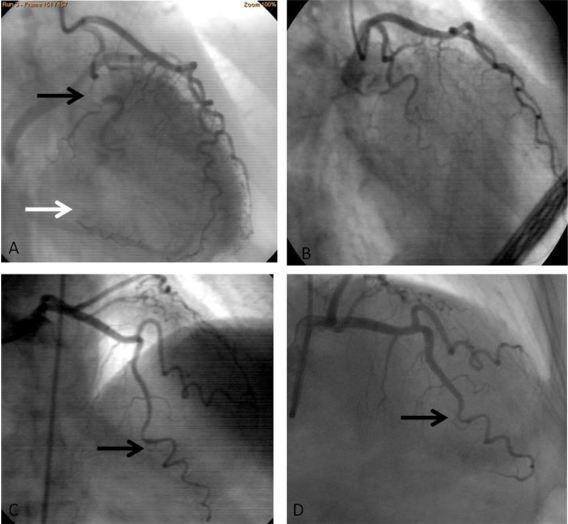

心尖部运动减弱。冠脉造影显示左前降支正常,右冠远端痉挛,回旋支远端弥漫性痉挛,注入硝酸酯类药物后痉挛缓解(图 1A)。

2 天后,患者出院,6 个月后再次因胸痛入院,期间无胸痛症状复发,入院心电图和超声心动图检查结果与第一次相似,冠脉造影显示回旋支、左前降支和右冠均正常(图 1B)。考虑诊断为回旋支和右冠新发痉挛,予钙离子拮抗剂治疗后出院。

1 周后,患者再次因相同症状入院,心电图检查提示 V3-V6 导联 ST 段压低,T 波低平,再次行冠脉造影显示回旋支和右冠正常,左前降支远端明显痉挛(图 1C),冠脉内注射硝酸酯类药物后缓解(图 1D)。2 天后患者出院并加大钙离子拮抗剂剂量。

图:冠脉造影检查结果